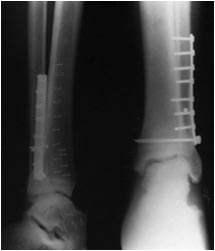

Re: Перелом лодыжек в сочетании с контрактурой 3-главой мышцы

Ну какой же это модный имплант? Заурядная треть-трубчатая пластина. С 2002 или 2003 г. я других и не ставил.

Медиальная лодыжка чуть не дорепонированв...

Прекрасно знаете, что такой миллиметр для внутренней лодыжки значения не имеет и на результате не скажется.

а где стягивающий винт?

Уверен, что с приходом фиксаторов с угловой стабильностью надобность в стягивающих винтах при переломах наружной лодыжки (особенно простых) полностью отпала. Уже много лет не ставлю их. Наверное, где-то еще работают по старинке.

Этот винт проведен через сам синдесмоз на 1 см проксимальнее сустава - а это в соответствии с какими рекомендациями?

Во вложении рентгенограмма из руководства Кэмпбэлла, издания 2013 г. (стр. 2623), демонстрирующая технику фиксации синдесмоза через отверстие в пластине. Расстояние от суставной линии там явно не 2 см. тем более не 3.